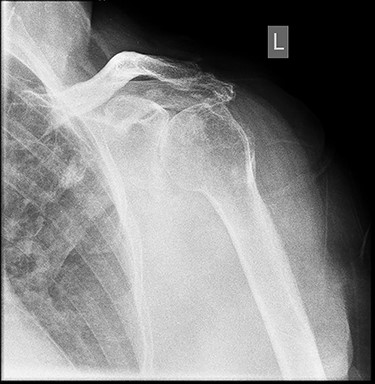

Six months post-surgery—profound loss of joint space and superior subluxation.

X-ray images 6 months later showed the devastating effect of the infection with a profound loss of joint space and superior subluxation in keeping with loss of rotator cuff muscles.